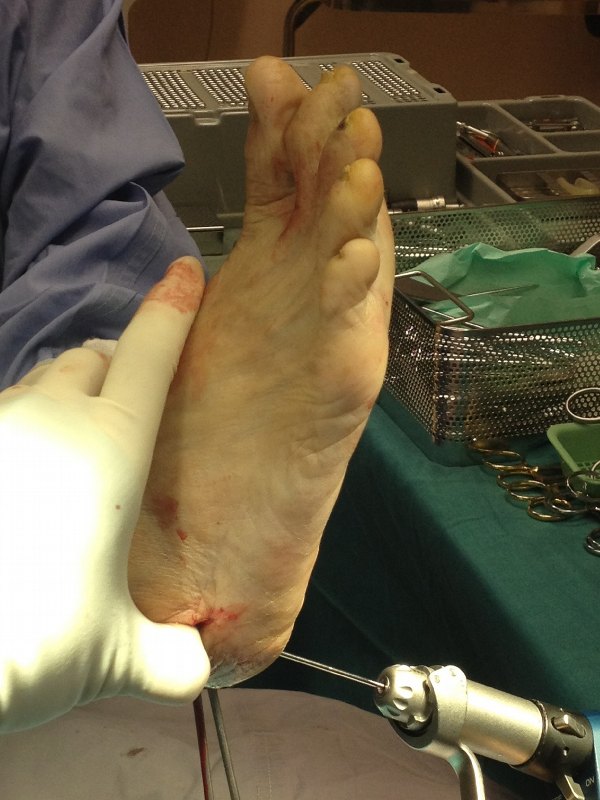

An incision is made on the outer aspect of the heel to expose the heel bone for the medial displacement calcaneal osteotomy.

A medial displacement of the cut heel bone is performed. The idea is to correct the heel valgus into neutral so that the patient walks with the heel in neutral and not pointing outwards which will stress the PTT.

The guidewire is inserted to stabilise the cut heel bone temporarily while a screw is being inserted for final fixation.

Note the correction of the right heel valgus into neutral.